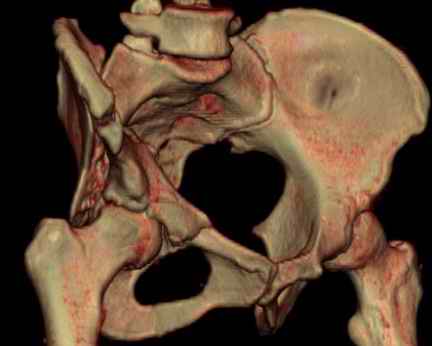

Посылаю схемы и 3D реконструкцию подобного повреждения. Называется он полным высоким двухколонным переломом вертлужной впадины, а "переломы крыла и тела подвздошной кости" входят в это понятие.

прикладываю схему доступа и случай.